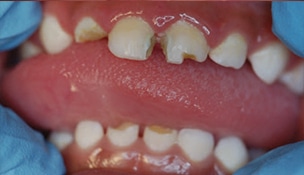

Severe ECC (S-ECC) is defined as any sign of smooth-surface caries in children younger than age 3. Additionally, in children ages 3 through 5, one or more dmf surfaces in primary maxillary anterior teeth, or a dmf score of ≥ 4 (age 3), ≥ 5 (age 4), or ≥ 6 (age 5) surfaces also constitutes S-ECC.3 The typical early sign of ECC is the crescent shaped white spot lesion at the gingival margin (Figure 1 to Figure 4).

According to the Agency for Healthcare Research and Quality sponsored United States Medical Expenditures Panel Survey, the average dental expense in 2004 for children younger than 6 was $186 per child.7 The total cost associated with care is estimated at slightly more than $1 billion annually.7 Treating ECC often requires extensive restorative treatment or the extraction of primary teeth. In addition to the expenses of dental restorations, general anesthesia or sedation may be required if children lack the ability to cope with dental procedures. General anesthesia to facilitate dental treatment may add anywhere between $1,500 and $6,000 to the cost of dental care.8 ECC also may contribute to other health problems, such as weight loss, however, the evidence for this is inconsistent.9 Sadly, ECC continues to be the most common chronic disease in children.10